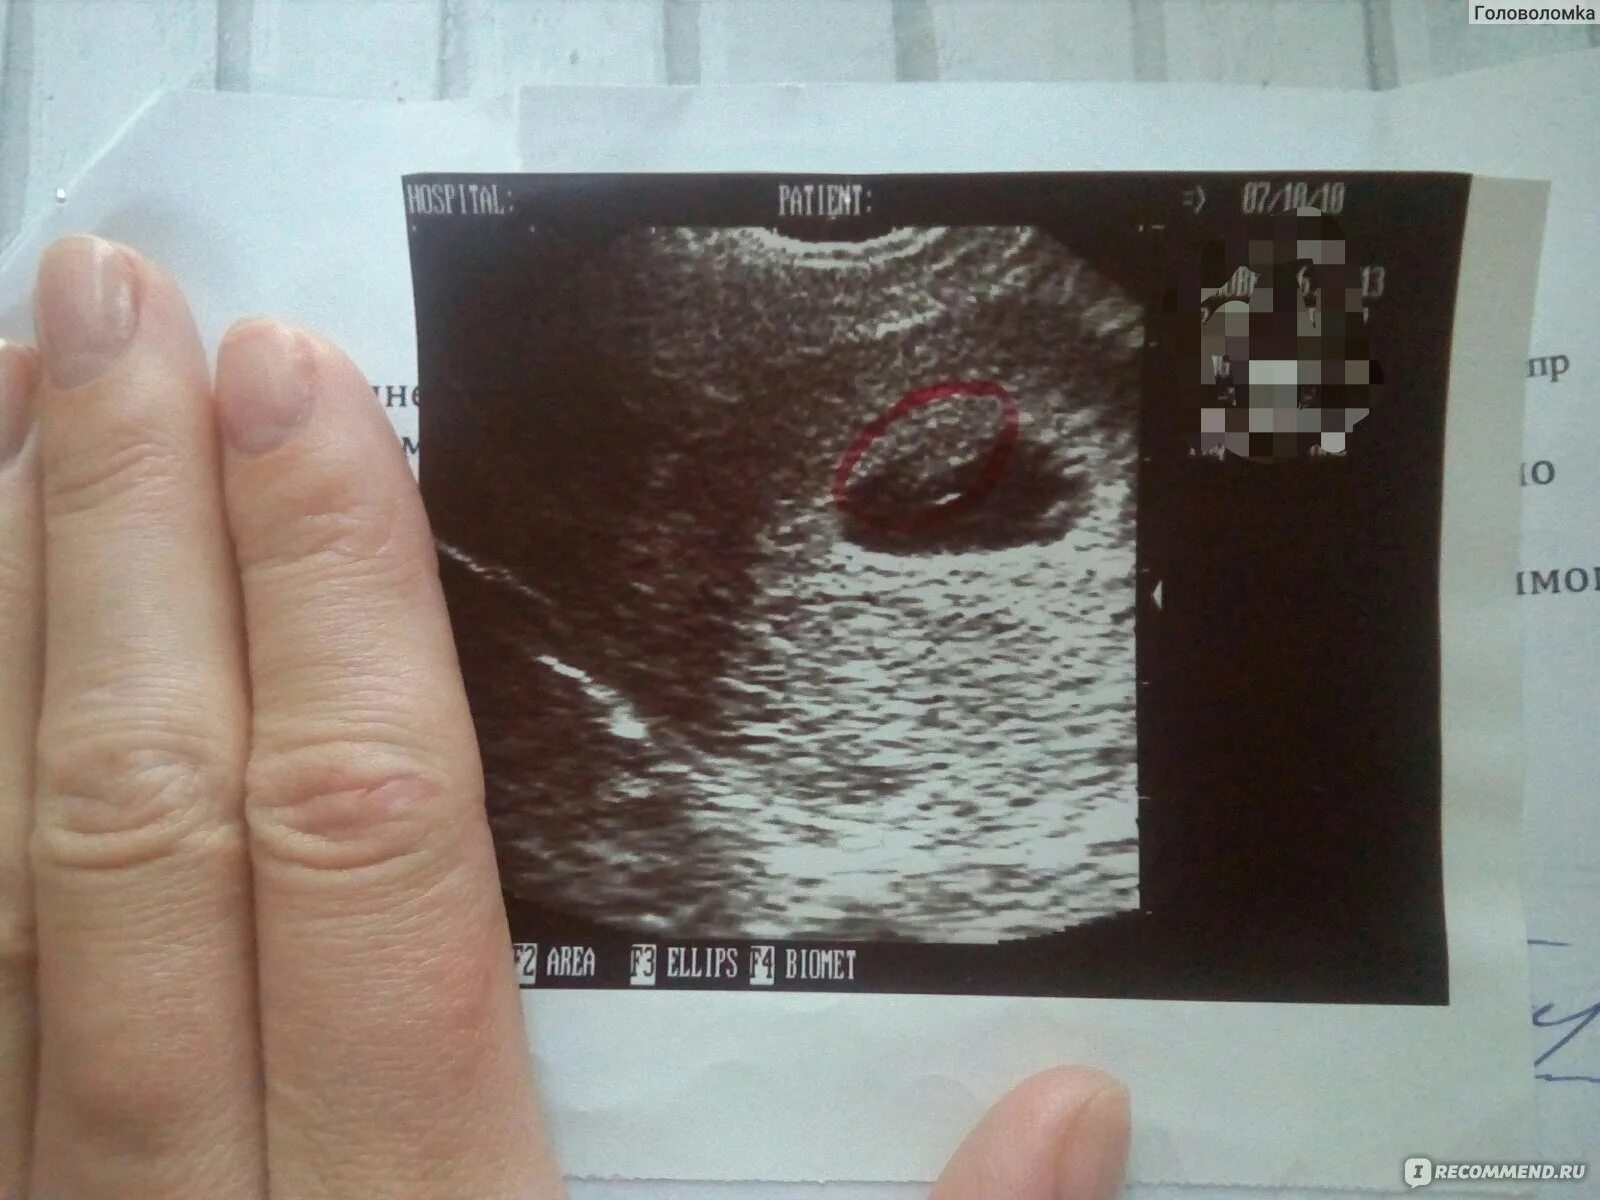

Цервикометрия как делают